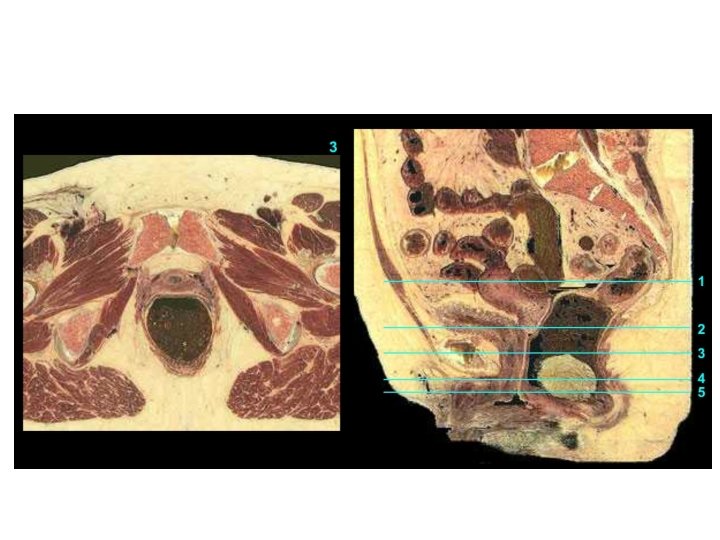

Frontaler Schnitt des weiblichen Beckens Anteile des weiblichen subperitonealen Raumes: -Paracysticum (um die Harnblase) -Paramerium (zwischen den Blättern des Lig. Latum uteri) -Paracolpium (um die Scheide) -Paraproctium( um das Rektum)

Vagina Excavatio vesicouterina Peritoneum Excavatio rectouterina Uterus Portio vaginalis cervicis Vesica urinaria Portio supravaginalis cervicis Fornix vaginae, Pars posterior Fornix vaginae, Pars anterior Vagina, Paries anterior Rectum Urethra Septum rectovaginale Septum vesicovaginale Vagina, Paries posterior Ostium vaginae Vestibulum vaginae Diaphragma urogenitale